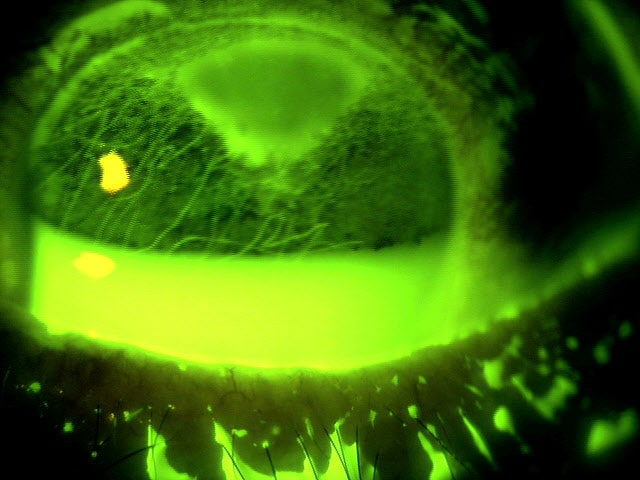

59歳 女性視力 右眼 0.06(1.0p×-3.25=c-2.50A150°) 左眼 0.03(0.2×-3.75=c-1.00A35°)主訴 左眼の視力低下で受診。 乳頭が下鼻側に傾斜し、下方に萎縮(PPA)がみられる。 両眼ともに、後部ぶどう腫staphylomaの上縁に一致して乳頭下縁から黄...